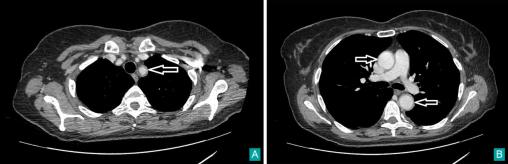

É. Crickx, La Revue du Praticien Scanner thoracique avec injection, montrant une vascularite de l’aorte et de ses branches.